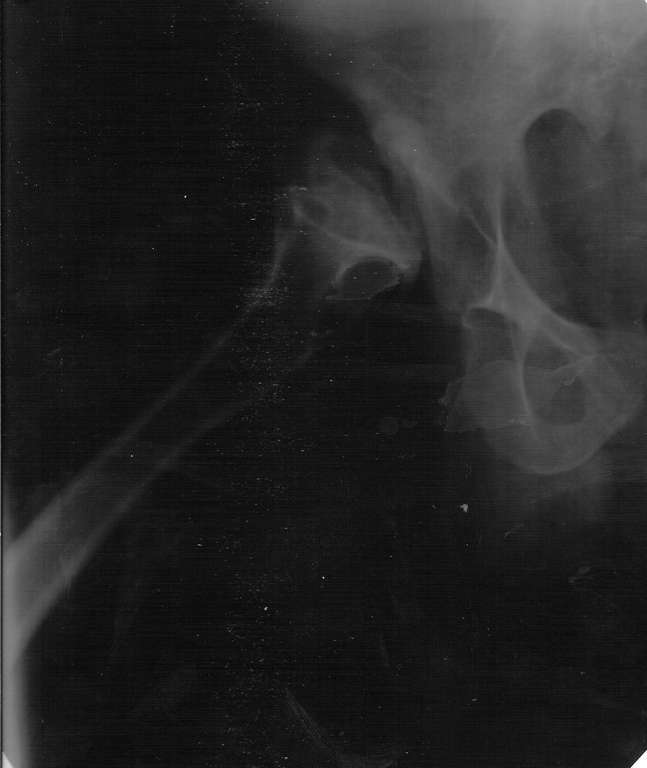

Здраствуйте, Уважаемые коллеги! Хотел бы вынести на обсуждения интересный случай. Больной 26 лет, наш коллега, с рождения диагноз Псевдохондродисплазия (карлик).

4 года назад начали беспокоить суставы, особого внимания не придавал - купировал болевой синдром. Недавно обратился с следующей картиной на рентген - снимках, имеется одинаковое укорочение обеих н/конечностей правой за счёт ас. некроза головки, левой - из-за варусной деформации голени.

Ваше мнения:

- нужно-ли эндопротезирование т/б, коленных суставов

- если да, то каким видом и типом протезов

- нужна-ли пластика крыши и дна вертлужной впадины

- другие альтернативные варианты